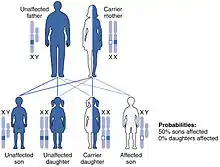

Inherited forms of leukodystrophy are usually the result of an autosomal recessive inheritance pattern, although dominant inheritance patterns are not unheard of, as in the case of adult-onset leukodystrophy.[13] This means that the affected allele is carried on an autosomal, or non-sex, chromosome and is masked by the dominant, unaffected phenotype. In other words, for an individual to inherit the leukodystrophy phenotype, he or she must carry two of the recessive, mutant alleles. Krabbe disease and metachromatic leukodystrophy (MLD) are two of such type. MLD is found on human chromosome 22 at position q13.31.[14] Another type of inherited leukodystrophy is X-linked adrenoleukodystrophy (X-ALD). As its name implies, this type of leukodystrophy is the result of a mutation found on the X-chromosome. It is also carried in a recessive pattern. The X chromosome is a sex chromosome, and since women have two "chances" of acquiring a normal X chromosome (one maternal x, one paternal x), and males only one chance (one maternal x), this disease is more likely to be seen in males than in females. The mutation resulting in adult-onset leukodystrophy is mapped at 5q23.[13]

Currently, no research has shown a higher prevalence of most leukodystrophy types in any one place around the world. There is, however, a higher prevalence of Canavan disease in the Jewish population. One in 40 individuals of Ashkenazi Jewish descent are carriers of Canavan disease.[28] This extrapolates to roughly 2.5%. Additionally, due to their autosomal recessive inheritance patterns, there is no significant difference found between males and females for most types of leukodystrophy, including but not limited to metachromatic leukodystrophy, Krabbe disease, Canavan disease, and Alexander disease. The one exception to this is any type of leukodystrophy carried on a sex chromosome, such as X-linked adrenoleukodystrophy, which is carried on the X-chromosome. Because of the inheritance pattern of X-linked diseases, males are more often affected by this type of leukodystrophy, while female carriers are often symptomatic, though not as severely affected as males.[29]